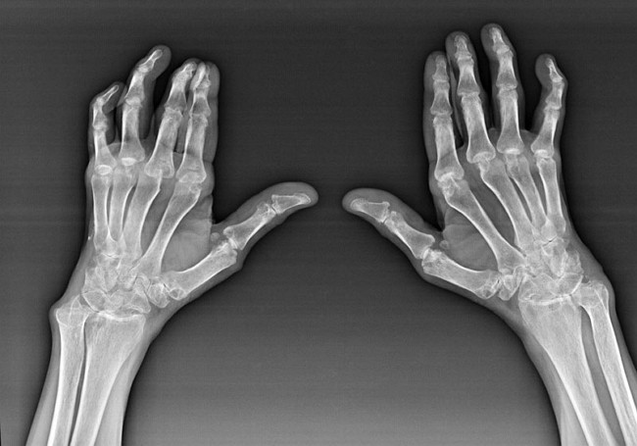

Reumatoidná artritída

Reumatoidná artritída je ochorenie, pri ktorom ľudský imunitný systém poškodzuje vlastné tkanivá tela. Inými slovami, reumatoidná artritída je autoimunitnou patológiou. Toto ochorenie je tiež systémové, pretože s ním je postihnuté mnoho tkanív (Svaly, kĺby, plavidlá atď.) a orgány (Srdce, obličky, pľúca atď.) v tele.

Napriek tomu, že reumatoidná artritída je pod ňou systémové ochorenie, vo väčšej miere trpia kĺby, zatiaľ čo lézia iných tkanív a orgánov je v pozadí. Pri tejto chorobe môžu byť ovplyvnené takmer všetky typy kefových kĺbov (zápästia, karpalské cesty, metacarpal-falanx, medzifalanxové kĺby). Lézia je zvyčajne symetrická (tie. Sú ovplyvnené rovnaké kĺby) na oboch rukách sprevádzané opuchom, bolesťou poškodených kĺbov. Ráno, počas zdvíhania z postele, je v postihnutých kĺboch určitá tuhosť, ktorá môže trvať asi 1 hodinu a potom zmiznúť bez stopy.

Pomerne často s reumatickou artritídou v blízkosti postihnutých kĺbov kefy (Častejšie klavírne kĺby, medzifálové kĺby) Sa objavujú reumatoidné uzly. Sú zaoblenou formáciou umiestnenou pod kožou. Na kefke sa tieto útvary objavujú najčastejšie na chrbte. Na palpácii sú husté, neaktívne, bezbolestné. Počet z nich sa môže líšiť.